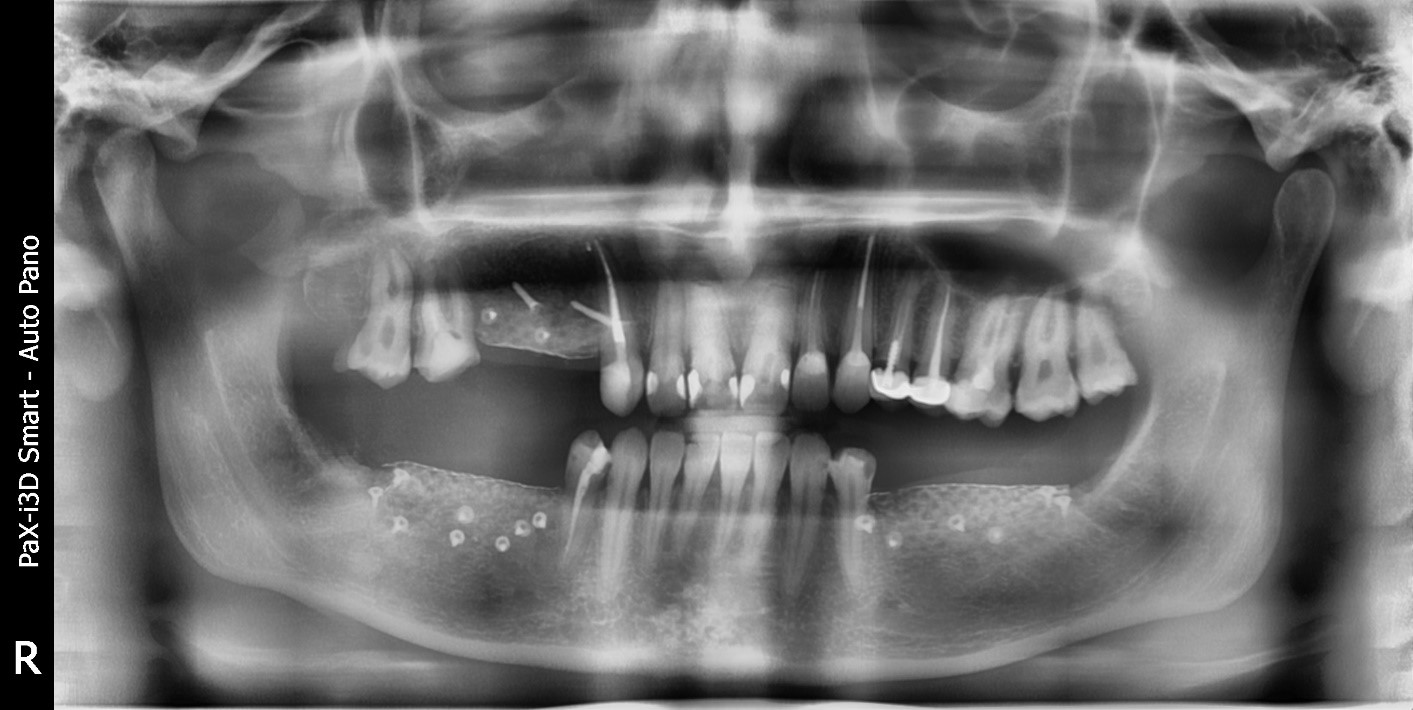

Это снимок ротовой полости другого пациента, которому показана костная пластика. На нижней челюсти справа и слева от оставшихся зубов кость просела, объём необходимо восполнить. Ниже при описании операции я покажу фото того же пациента после операции.

До костной пластики

Вертикальная пластика — это когда костного материала не хватает по высоте. Есть ещё пластика горизонтальная, в этом случае объём кости недостаточен по ширине. Например, когда гребень практически острый, его расщепляют, раздвигают, засыпают внутрь костную стружку и закрывают мембраной.

На верхней челюсти вертикальная пластика нужна очень редко, почти никогда. Потому что за счёт мощного кровоснабжения на верхней челюсти кость по вертикали не рассасывается. Там если что и нужно, то горизонтальная пластика или синус-лифтинг — наращивание костной ткани в области гайморовых пазух.

Так что вертикальную пластику мы обычно делаем на нижней челюсти. Это сложнее, потому что обязательно нужен каркас, защищающий новую молодую кость от нагрузки сверху. Когда мы увеличиваем объём по горизонтали, давление сверху приходится на собственную кость, а боковой нагрузки практически нет. А при вертикалке нужна защита. А ещё нужно десну на новую кость натянуть и ушить так, чтобы ничего не оголилось: тоже задача не из простых.